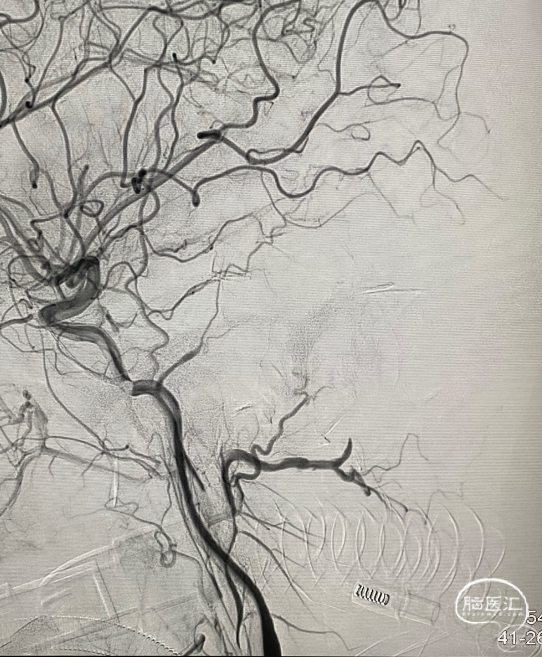

第一台手术结束。开始第二台,一个复发大脑中动脉瘤,复发部位虽然不大,但毕竟是出血动脉瘤,还是远期继续增大再出血的风险。

Lvis jr小支架辅助小弹簧圈栓塞,很好的解决的复发部分。

再次造影,没有动脉瘤的显影了,远期再复发的几率就很小了。